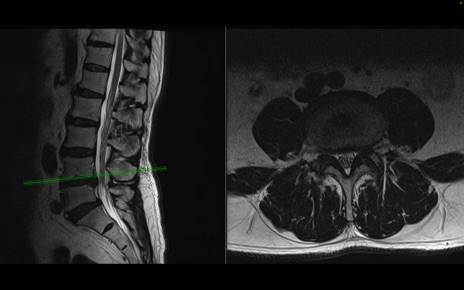

【整形】TIPS症例2 腰椎MRI 横断像と矢状断像

【症例】70歳代男性

【主訴】左下肢痛

【現病歴】2週間前くらいから腰痛、左下肢痛あり。左臀部から大腿、下腿外側のしびれが常時ある。歩行とともに同部位の痛みあり。

【身体所見】Lasegue70-/60+、Bragard-/±、PTR ±/±、ATR -/-、IP 5/5、TA 5/4、TS 5/5、EHL 右第1足趾なし/3、FHL 5/5、hypersthesia(-)、足背動脈触知良好

異常所見と診断は?